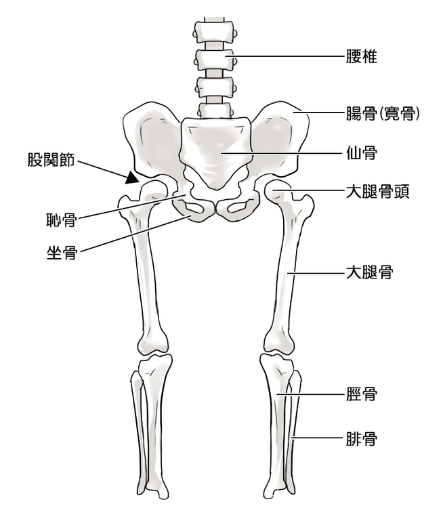

これまで原因不明とされた股関節痛の中にも、「股関節唇損傷」が含まれていると言われており、現在注目を集めています。股関節唇損傷について説明します。

股関節唇とは、骨盤側の寛骨臼の辺縁を取り巻く柔らかい軟骨で、リング状のゴムパッキンのように大腿骨頭を包み込んでいる部分のことです。 大腿骨頭を安定化させ、衝撃吸収の役割を担っています。 関節唇には神経が存在し、損傷を受けると痛みが生じることがあります。 関節唇損傷が生じると骨頭が安定しなくなり、次第に軟骨が破壊され、変形性股関節症へ移行すると考えられています。

特発性大腿骨頭壊死症

特発性大腿骨頭壊死症は、血液が行き渡らなくなることで骨が壊死し、そこが突然に骨折して、股関節が痛くなる希少疾患です。現在(2017年)、国の難病にも指定され、原因究明や治療方法などさまざまな側面から研究されています。

血液の流れが悪くなることによって、骨が死んでしまう

特発性大腿骨頭壊死症とは、骨の一部である大腿骨頭の血流が悪くなることによって壊死し、最終的には壊死部の骨折や骨頭の圧潰を起こす疾患です。大腿骨頭は、股関節にある大きなボール状の骨のことを指し、骨盤と大腿骨をつなぎ、上半身の体重を支える役割をしています。